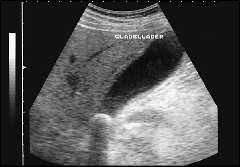

Классической ультразвуковой картиной желчного конкремента являются плотная структура, визуализация только его передней поверхности и акустическая тень на всю ширину камня. При перемене положения тела конкремент смещается. При визуализации конкрементов нужно помнить, что они располагаются в наиболее отлогих местах. Если пациент на исследование пришел самостоятельно, то наиболее вероятным положением конкрементов является область дна, если доставлен на каталке, возможно любое положение камней, в том числе в кармане Гартмана. Для тщательного поиска желательно переменить положение тела пациента: подвижный камень передвинется, фиксированный камень останется на месте. Причинами фиксации может быть ущемление в шейке или формирование местных изменений желчного пузыря в области конкремента. Размеры желчных конкрементов бывают различные. Наименьшие конкременты, которые могут быть визуализированы на современных диагностических приборах, имеют размеры до 2–3 мм. Крупные конкременты могут занимать весь просвет пузыря, последний утрачивает свою работоспособность. Крупные конкременты могут травмировать стенку пузыря, приводить к формированию пролежней, считаются предрасполагающим фактором развития рака желчного пузыря. Мелкие конкременты наиболее опасны, так как могут войти в пузырный проток, диаметр которого около 3 мм, царапнуть стенку и привести к спазму протока. Со спазма протока начинается развитие желчной колики. Определенные трудности представляет диагностика множественных конкрементов, прилегающих друг к другу и заполняющих весь просвет пузыря, желчь в нем отсутствует. В этом случае при ультразвуковом исследовании видна передняя стенка пузыря, за ней определяется зубчатая поверхность переднего ряда камней, дистальнее определяется акустическая тень на всю ширину пузыря. Определить размеры каждого из конкрементов в таком пузыре не представляется возможным, обычно достаточно указать размер наибольшего и наименьшего конкрементов. Иногда возникают сложности при визуализации очень мелких конкрементов, которые имеют маленькие размеры и находятся на дне, или передвигаются в виде маленькой «дорожки камней» с тенями, сливаясь с газосодержащими петлями кишечника у стенки пузыря. Такие конкременты требуют внимания и тщательного полипозиционного исследования. Конкременты могут выходить из желчного пузыря в общий желчный проток, это приводит к увеличению его диаметра. При ультразвуковом исследовании, на фоне желчи, в протоке визуализируется конкремент различных размеров, обычно соответствующих размеру холедоха. Камни холедоха могут не затруднять отток желчи, могут быть вентильными, при определенном повороте приводить к перекрытию просвета, или полностью перекрывать его, приводя к развитию гипертензии желчевыводящих путей и механической желтухе. Конкременты в холедохе могут быть множественными, прилегать друг к другу, иметь фасетчатое строение и полностью закупоривать просвет. Камень может быть ущемленным в дистальной части холедоха и в ампуле большого дуоденального соска, также приводя к гипертензии желчевыводящих путей и развитию холестаза. При ультразвуковом исследовании конкремент в ампуле или дистальной части холедоха лучше визуализируется на срезах головки поджелудочной железы в интрапанкреатической части холедоха. Он лоцируется как акустически плотная структура с тенью, заполняющая просвет расширенного холедоха.

Принципы диагностики конкрементов в долевых желчевыводящих путях и общем печеночном протоке подобны: конкременты присутствуют в расширенных желчевыводящих протоках, последние идут рядом с крупными портальными стволами в печеночных триадах. Осложнениями желчекаменной болезни являются желчная колика, острый холестаз, водянка желчного пузыря и сморщенный желчный пузырь; острый и хронический калькулезный холецистит – тоже осложнения желчекаменной болезни, но их обычно рассматривают как воспалительные заболевания. В случае, если конкремент нарушил пассаж желчи частично, спазм не возникает, воспалительные изменения выражены слабо, возможно развитие водянки желчного пузыря, обычно это происходит у пожилых пациентов с низкой двигательной активностью. При ультразвуковом исследовании желчный пузырь с конкрементами значительно увеличен, стенки его не утолщены, имеются конкременты, но жидкостное содержимое достаточно однородное. Водянка желчного пузыря может перейти в эмпиему, тогда при ультразвуковом исследовании стенки увеличенного пузыря утолщаются, содержимое становится неоднородным, с мелкодисперсной взвесью и сгустками, определяются конкременты, иногда возможно расслоение жидкости с формированием эхогенного уровня. При заполнении просвета желчного пузыря конкрементами формируется отключенный желчный пузырь. Если один из конкрементов перекрыл проток, желчный пузырь отключен, уменьшен в размере, сморщен. При ультразвуковом исследовании визуализируется уменьшенный пузырь, содержащий конкременты, но не содержащий желчи. Стенки его обычно утолщены, может присутствовать воспаление разной степени выраженности. Продвижение конкремента в общий желчный проток может привести к развитию острого холестаза с последующей механической желтухой. Под острым холестазом понимают клиническую ситуацию, когда в результате остро возникшей обструкции холедоха прекращен отток желчи в двенадцатиперстную кишку. У пациента присутствуют болевой синдром в правом подреберье и механическая желтуха. В случае, если причиной холестаза являются конкременты, при ультразвуковом исследовании необходимо исследовать внутрипеченочные желчные протоки, холедох и желчный пузырь. Выраженность картины острого холестаза зависит от его временной протяженности. Обычно в начале заболевания пациент испытывает болевой приступ в правом подреберье разной степени выраженности. В первые часы после приступа при ультразвуковом исследовании выявляются расширенный холедох и увеличенный желчный пузырь с конкрементами, возможна визуализация конкремента в холедохе. Если пациент поступает на обследование примерно через сутки после начала приступа, клинически у него присутствует желтуха кожных покровов или иктеричность склер, появляется расширение внутрипеченочных желчных протоков. При ультразвуковом исследовании расширенные протоки визуализируются, как вторые трубчатые структуры, располагающиеся рядом с ветками портальных вен всех уровней. Чем более длительный холестаз, чем выше уровень желчных пигментов в крови, тем шире протоки, их диаметр приближается к диаметру соответствующих портальных вен. Камень в холедохе может быть вентильным, то есть просвет протока периодически может восстанавливаться, если камень поворачивается другим боком. В такой клинической ситуации признаки холестаза могут быть выражены слабее. Желтуха может то нарастать, то ослабевать, соответственно этому меняется выраженность описанных ультразвуковых признаков.